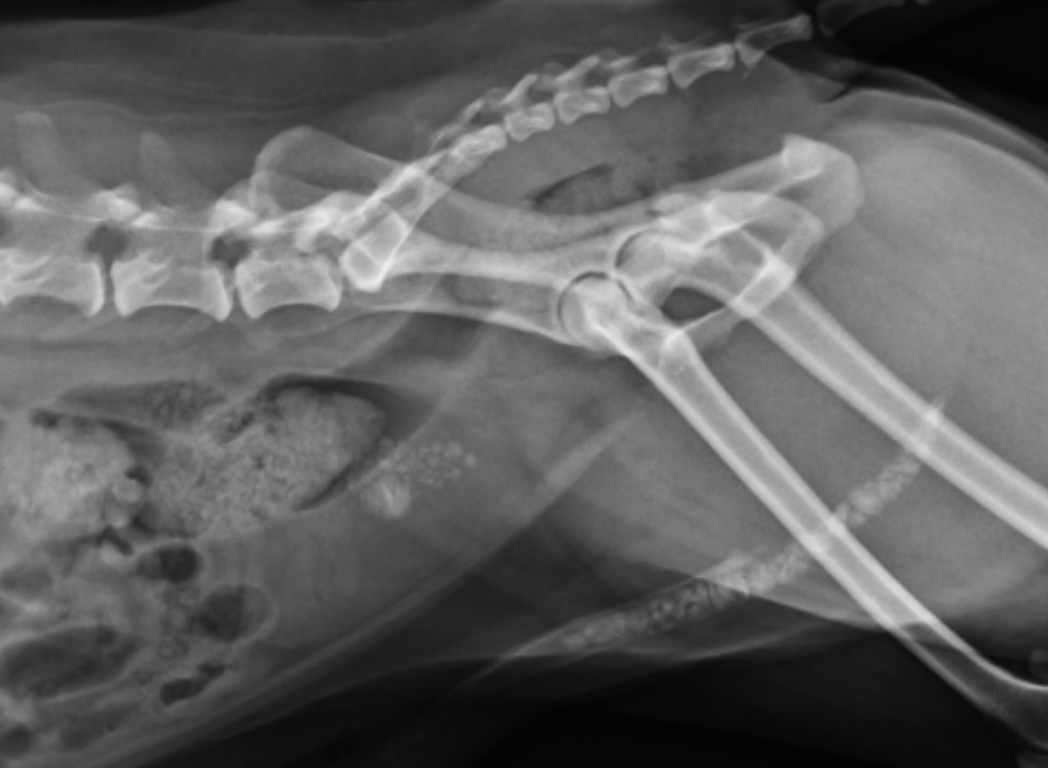

• 外力撞擊造成肱骨骨折的喵咪 右肘關節脫位 手術完整的復位 小腸異物阻塞

外力撞擊造成肱骨骨折的喵咪 右肘關節脫位 手術完整的復位 小腸異物阻塞